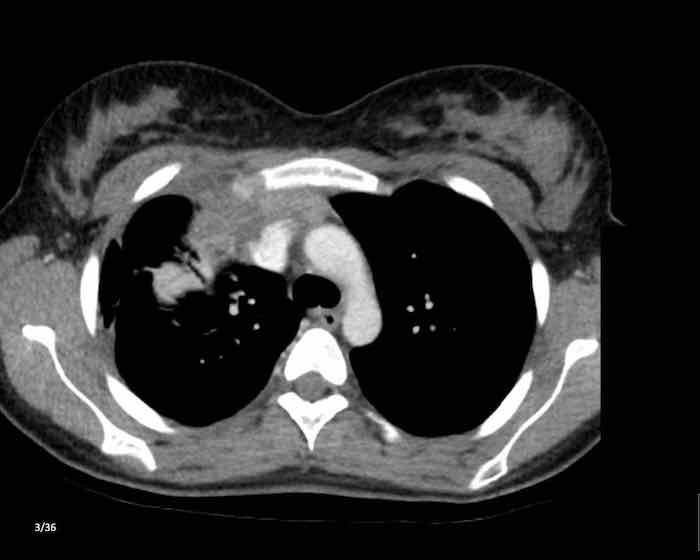

Các hình ảnh này của một nam giới 19 tuổi, được chụp CT để loại trừ thuyên tắc phổi.

Phát hiện tình cờ một khối ở khoang trước mạch máu.

Chẩn đoán có khả năng nhất là tăng sản tuyến ức và MRI được thực hiện để phân biệt thêm khối này.

Trên hình ảnh chuỗi xung T2W, tổn thương có tín hiệu tăng nhẹ.

Trên hình ảnh pha đối (out-of-phase), không có sự sụt giảm tín hiệu đáng kể.

SII nhỏ hơn 9%.

Do bệnh nhân không có bất kỳ triệu chứng nào, đặc biệt không có các triệu chứng có thể liên quan đến u lympho, và vì u tuyến ức (thymoma) là một khối u hiếm gặp, quyết định được đưa ra là theo dõi sau sáu tháng.

Tại thời điểm theo dõi sáu tháng, tuyến ức có hình ảnh bình thường.

Kết luận được đưa ra là đây là tăng sản tuyến ức hoặc mô tuyến ức tồn dư kích thước lớn, đã thoái triển trong vòng sáu tháng.